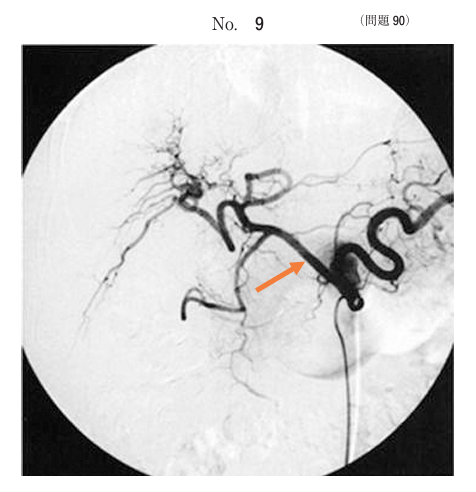

午前/問題90

血管造影写真別冊No. 9 を別に示す。矢印で示すのはどれか。

1.脾動脈

2.左胃動脈

3.総肝動脈

4.固有肝動脈

5.胃十二指腸動脈